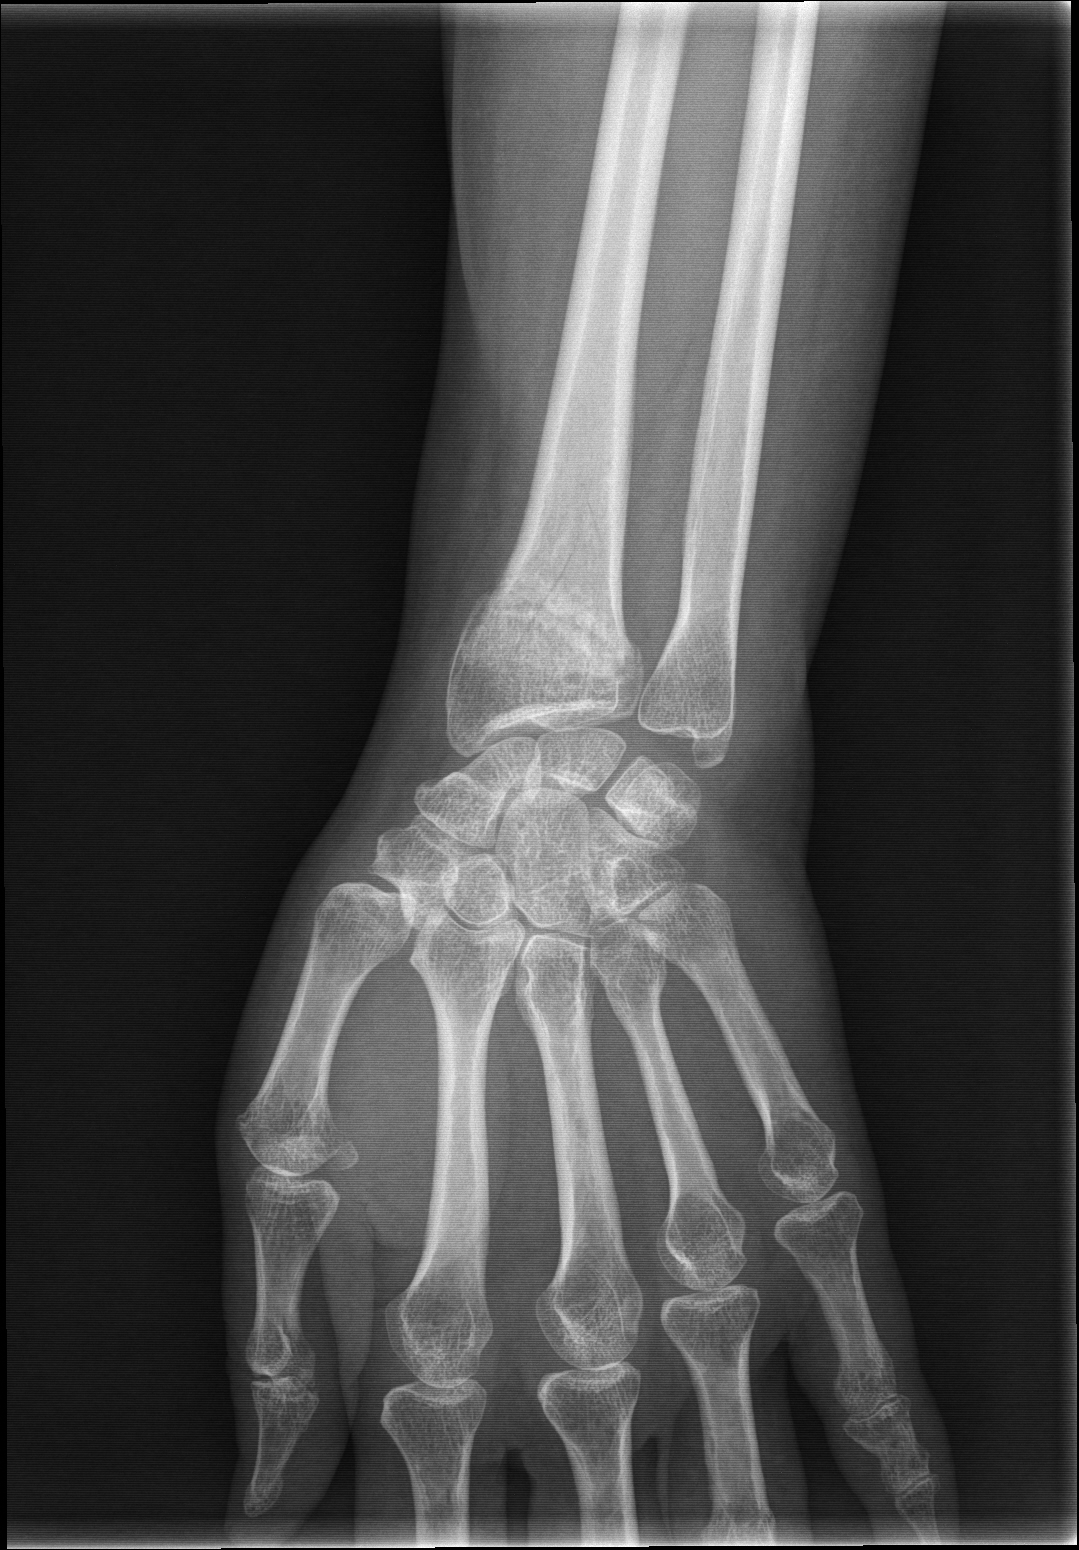

Xray image of wrist joint front view of normal wrist joint Stock Photo Wrist X Ray Technique The pa wrist radiograph is requested for myriad reasons including but not limited to trauma, suspected infective processes, injuries the distal. With the increased use of dorsal distal radial plate and screw fixation for distal radial fractures, there is a need for improved accuracy in imaging the wrist. Imaging techniques play an important role in evaluating the complex anatomy of. Wrist X Ray Technique.